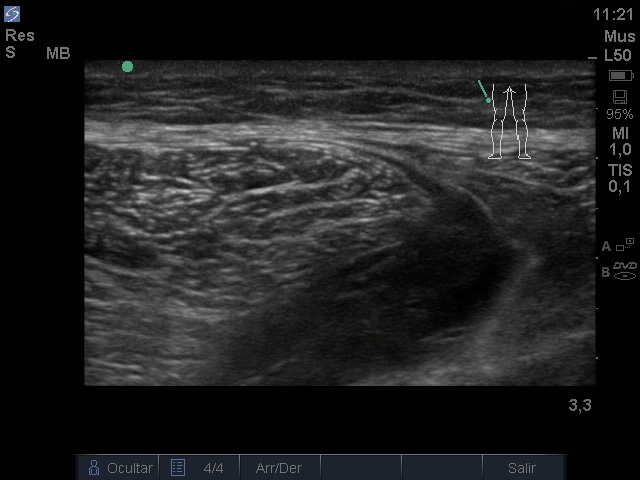

Ecografía: discontinuidad de la disposición de las fibras musculares normales a nivel del tercio medio de los cuerpos musculares isquiosurales que afecta al músculo semitendinoso del miembro ingerior izquierdo, edema focal e imágenes.

Anecogénicas intramusculares, sin captación doppler.

Se observa imagen anecoica irregular, elipsoide que se interpreta como sangrado entre el músculo semitendinoso y semimembranoso.